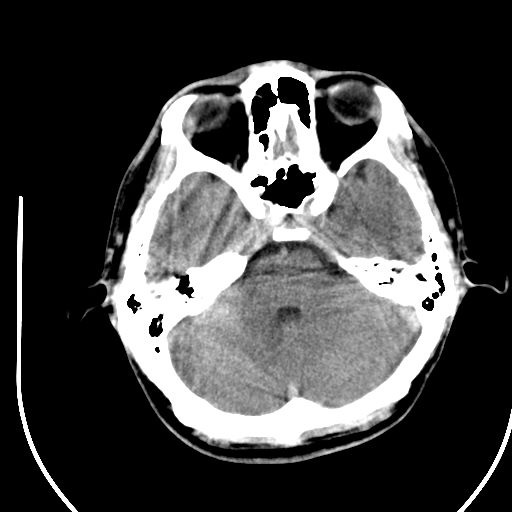

标题: CT28158:男,27Y。头痛数月,左顶叶血管瘤。 [打印本页]

标题: CT28158:男,27Y。头痛数月,左顶叶血管瘤。

考虑avm。

考虑avm。  建议dsa检查。

海绵状血管瘤

考虑左顶叶海绵状血管瘤,建议mr检查。

考虑血管畸形,因其周可见水肿,不除外感染性病灶。建议mri检查。